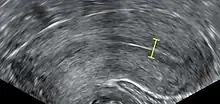

IVF may be used to overcome female infertility when it is due to problems with the fallopian tubes, making in vivo fertilisation difficult. It can also assist in male infertility, in those cases where there is a defect in sperm quality; in such situations intracytoplasmic sperm injection (ICSI) may be used, where a sperm cell is injected directly into the egg cell. This is used when sperm has difficulty penetrating the egg. ICSI is also used when sperm numbers are very low. When indicated, the use of ICSI has been found to increase the success rates of IVF.